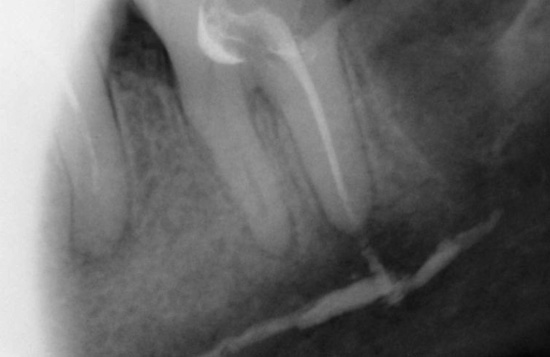

Lascando uma ferramenta em um canal

Se durante a limpeza do canal uma parte do instrumento endodôntico se romper nele, se for deixado no canal, o dente começará a doer imediatamente ou após algum tempo. Isso se deve ao fato de que um pedaço do instrumento preso no canal não dá ao médico acesso ao ápice da raiz, devido ao qual permanece uma parte do nervo ou uma infecção não tratada que começará necessariamente a se multiplicar e pode levar a problemas muito grandes no futuro.

Para evitar possíveis complicações futuras, a remoção imediata dos detritos é realizada usando vários métodos. Por exemplo, o método ultrassônico de "nocautear" um fragmento é atualmente usado ativamente. Outro método de extração é passar um canal ao lado de uma ferramenta presa, expandir, enxaguar, agarrar e removê-lo.

Se for impossível extrair, métodos cirúrgicos conservadores podem ser usados quando a parte passada do canal é selada com cimento e a parte onde o fragmento está localizado é ressecada (a ponta da raiz do dente é cortada).